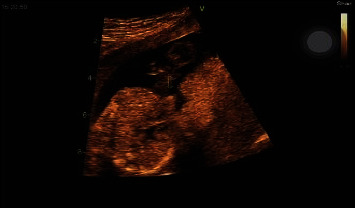

Methods: A 17-week-old female neonate with a history of prenatal diagnosis of congenital heart anomaly was admitted to Ayatollah Mousavi Hospital in Zanjan, Iran. For the diagnosis of thoracic ectopia, cordis fetal echocardiography and ultrasonography were performed. Moreover, the noninvasive prenatal testing (NIPT) genetic test performed in the 10th week of pregnancy was evaluated.

Results: The neonate was diagnosed with thoracic ectopia cordis, with the heart located outside the thoracic cavity and covered by a thin membrane. The Z scores of the analyzed maternal venous blood chromosomes were between +6 and -6, and all chromosomes had a low risk in terms of the risk of birth defects. The results of this study revealed that genetic test analysis is not enough to diagnose and predict congenital anomalies and defects. Furthermore, the findings showed that the fetus's mother continued to take folic acid after the first 3 months of pregnancy. This can be one of the risk factors involved in causing this heart defect.

Conclusion: One of the important results of this study was that the diagnostic findings of ultrasound were normal, but the findings of echocardiography were reported as abnormal. This shows that fetal echocardiography is better than ultrasound imaging in diagnosing ectopia cordis. In addition, it is recommended that pregnant women should avoid taking folic acid after the first trimester of pregnancy.